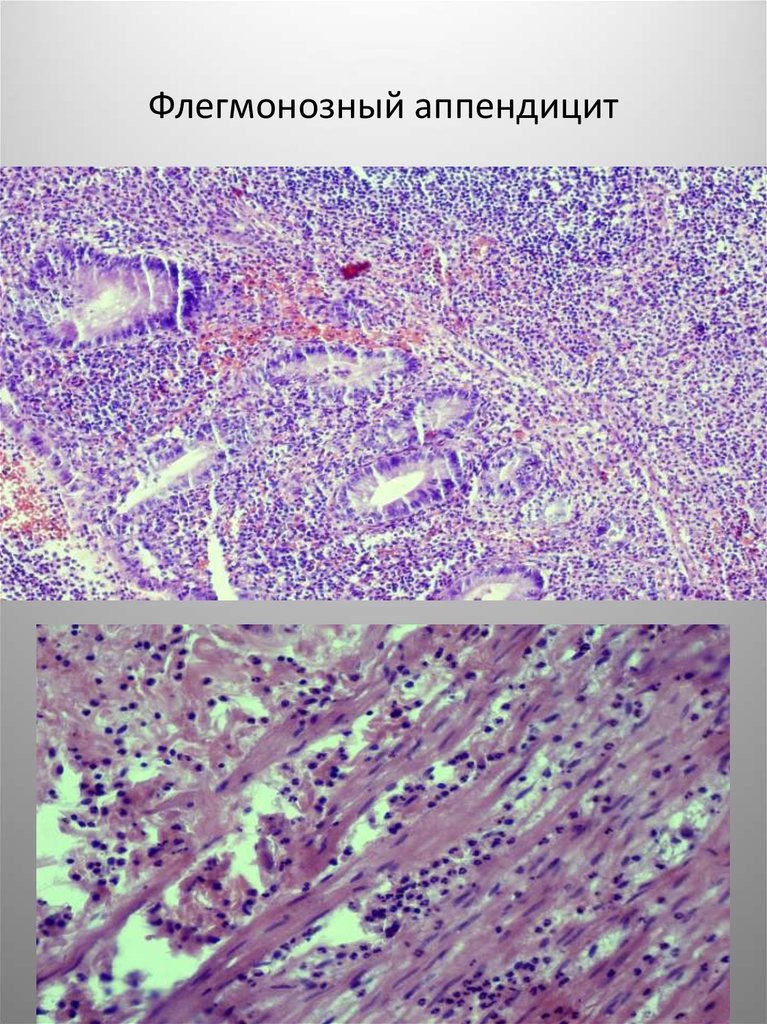

Флегмонозный

аппендицит

Флегмонозный аппендицит